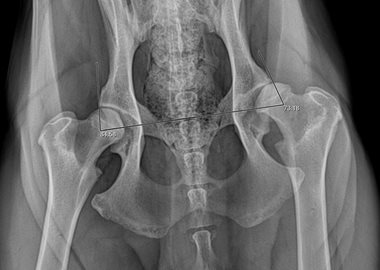

Malformation des hanches chez un chiot  - Clinique du Vernet Prothèse totale de hanche - Clinique du Vernet

Fig 1: Malformation des hanches chez un chiot de grande race de 6 mois par la Méthode PennHIP. Sur la radiographie les têtes fémorales sortent totalement de l’articulation (Dysplasie des hanches).

Fig 2: Prothèse totale de hanche haut de gamme, non cimentée, vissée, de 6ième génération mis en place par le Dr Guénégo lors de malformation sévère chez le jeune, d’arthrose ou luxation/fracture chez l’adulte ou le vieux chien